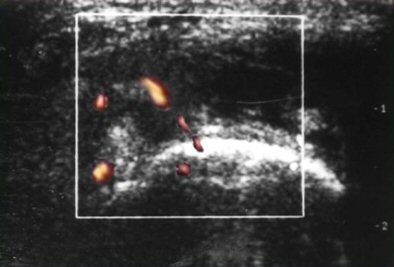

![]() |

| PDS reveals normal vascularity. |